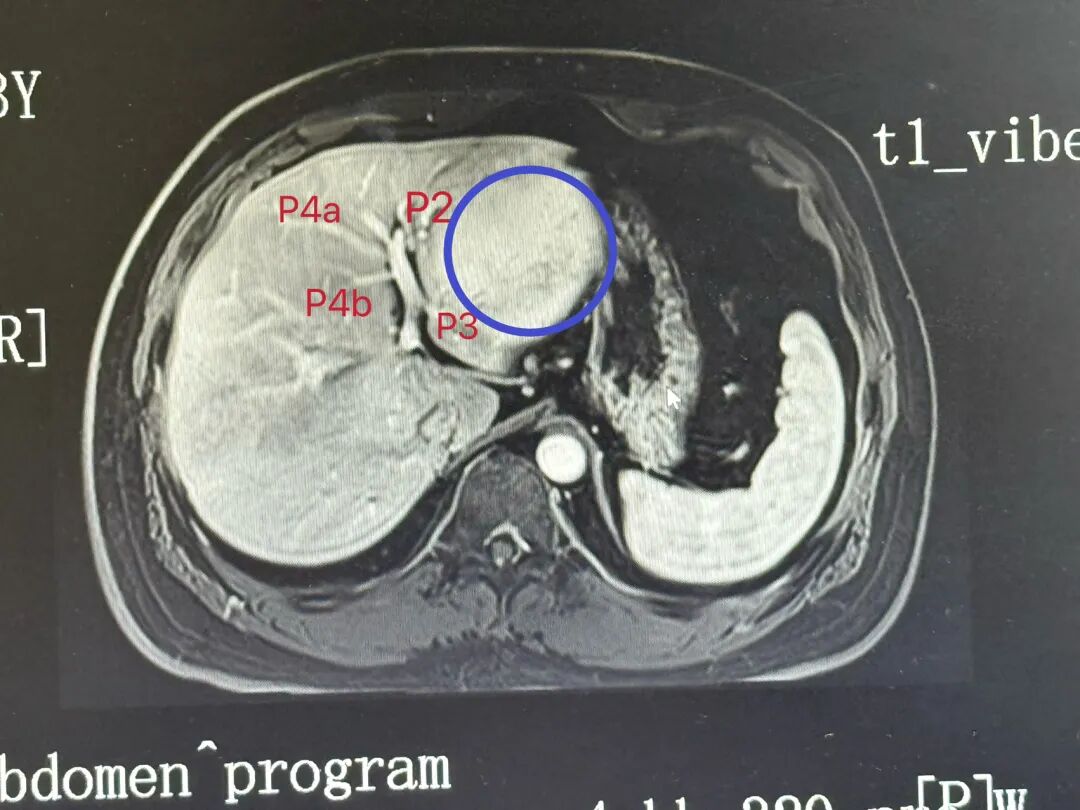

影像评估与手术规划:LHV没有显影,MHV、UFV完整,肿瘤位于矢状部左侧,P4ab完整。我的计划做左外叶可解决问题。

我们常规取五孔法入腹,离断并提起肝圆韧带,于鞘外贯通GateI-GateII,过7号丝线后以切缝离断,镰状韧带左侧缘结合缺血线,由足侧往头侧、从腹侧至背侧劈肝,于第二肝门处显露MHV与LHV的汇合部,以切缝离断LHV,整个手术40min结束,术后病检肝腺瘤。